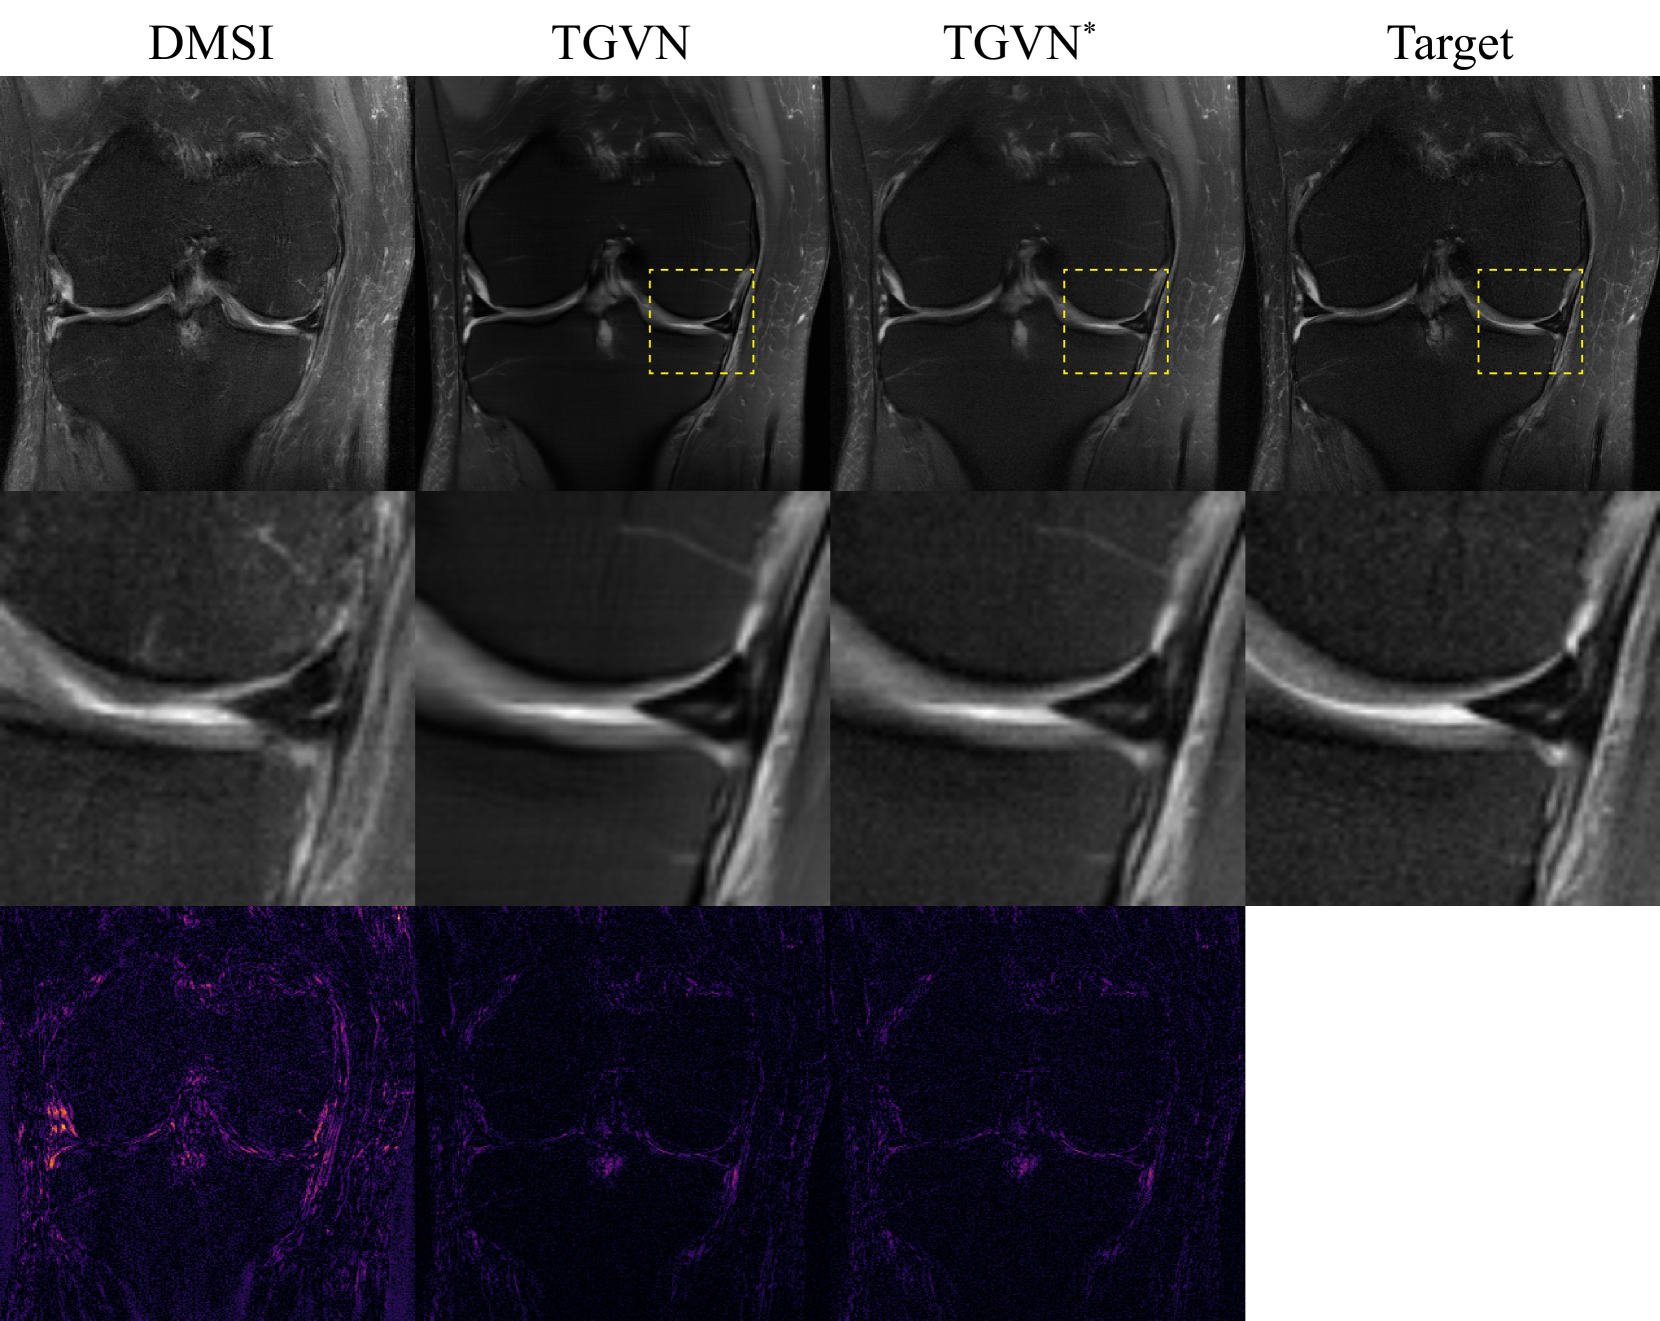

We applied an overall 20×20\times20 × undersampling mask to the PDFS measurements, with random outer undersampling and a 3%percent33\%3 % fully-sampled center. A 2×2\times2 × equispaced under-sampling mask with no fully-sampled center was applied to the PD measurements. Fig. 3(a) shows the reconstruction results for coronal PDFS images with and without using the side information. At 20×20\times20 × acceleration, side information aids the reconstruction significantly while reconstruction without side information results in the loss of various essential features. Fig. 4 compares TGVN reconstructions with reconstructions using multiple baselines that use side information. MTrans and MCVN exhibit significant blurring of anatomical features, and DMSI suffers severely from noise amplification, which is seen clearly in the absolute difference images. The output of TGVN is significantly superior: both overall sharpness and assorted anatomical details are better preserved in the TGVN reconstructions. Furthermore, the meniscus tear region is distinctly more noticeable with TGVN, highlighting that it is more effective in leveraging the side information to preserve key features in the image despite highly sparse measurements.

Refer to caption

Figure 4: Knee image reconstructions from Set I showing the effectiveness of TGVN in leveraging side information. TGVN is able to reconstruct a high-quality image even at challenging acceleration levels of 20×20\times20 ×, in comparison to various baselines. The meniscus tear, illustrated in the ground truth image and reconstructions with a yellow arrow, is notably more visible in the TGVN reconstruction than in baseline reconstructions. Top: Full field of view images. Middle: Zoomed-in regions indicated by dashed yellow boxes in the top row. Bottom: Absolute differences between each reconstruction and the ground truth, with a consistent color mapping to highlight error magnitudes. TGVN has the smallest error.